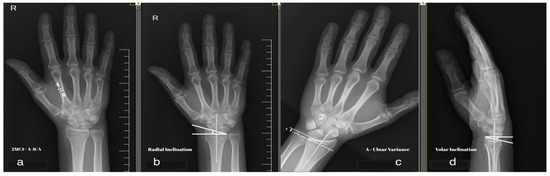

Second Metacarpal Index as a Predictor of Secondary Displacement in Conservatively Treated Distal Radius Fractures

by Alexandru Jecan, Gheorghe Tomoaia, Răzvan Marian Melinte, Diana Jecan-Toader, Roxana Cristina Rad Bodan and Daniel Oltean-Dan

Medicina 2026, 62(1), 105; https://doi.org/10.3390/medicina62010105 - 2 Jan 2026

Background and Objectives: Distal radius fractures (DRFs) represent the most common fracture in the elderly population and are typically the first fractures to occur in the sequence of fragility fractures. Although fracture instability is an important criteria for guiding treatment, there is no [...] Read more.

Background and Objectives: Distal radius fractures (DRFs) represent the most common fracture in the elderly population and are typically the first fractures to occur in the sequence of fragility fractures. Although fracture instability is an important criteria for guiding treatment, there is no universal consensus on how to define an unstable DRF. Given the demonstrated influence of bone quality on fracture stability, it has been hypothesized that second metacarpal index (2MCI) may also serve as a predictor of instability in DRFs. This study aimed to evaluate the predictive value of 2MCI for fracture instability and to determine its threshold value beyond which surgical management should be considered. Materials and Methods: A retrospective study was conducted between January 2023 and May 2025 investigating conservatively treated DRFs. Radiographic parameters including 2MCI, volar inclination, radial inclination, and ulnar variance were obtained at three time points: pre-reduction, post-reduction, and at 6 weeks of follow-up time. Univariate and multivariate linear regression analysis and receiver operating characteristic (ROC) analysis were conducted to determine the optimal 2MCI threshold for predicting clinically significant displacement. Results: A strong correlation was found between 2MCI and the changes (∆) in volar inclination (p < 0.001), radial inclination (p < 0.001), and ulnar variance (p < 0.001) in univariate regression analysis. In multivariate regression analysis, 2MCI was an independent predictor of ∆ volar inclination (p < 0.001) and ∆ radial inclination (p = 0.004). For ∆ ulnar variance, both 2MCI (p = 0.003) and initial displacement (p = 0.049) were statistically significant predictors. A 2MCI cut-off value of 0.412 predicted a ∆ volar inclination greater than 10° (sensitivity 80.9% and specificity 74.1%, p < 0.001). Conclusions: The results of this study reveal the potential of the 2MCI as a quantitative marker of both fracture instability and bone fragility. Further prospective validation may demonstrate its role as a standard radiographic parameter in DRFs, as well as in guiding treatment selection. Full article

(This article belongs to the Section Orthopedics)

Show Figures

Figure 1